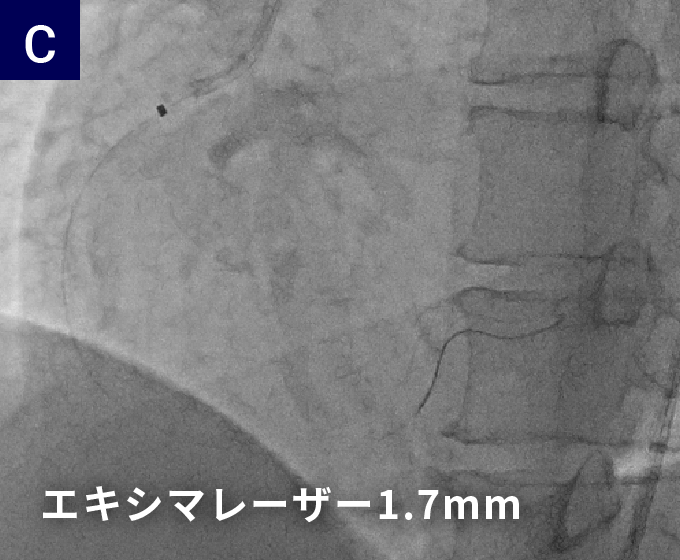

40代男性急性心筋梗塞で救急搬送

右冠動脈に対するエキシマレーザーを使用したPCI

レーザー前

レーザー後

バルーン拡張後

1週間後

株式会社フィリップス・ジャパン提供